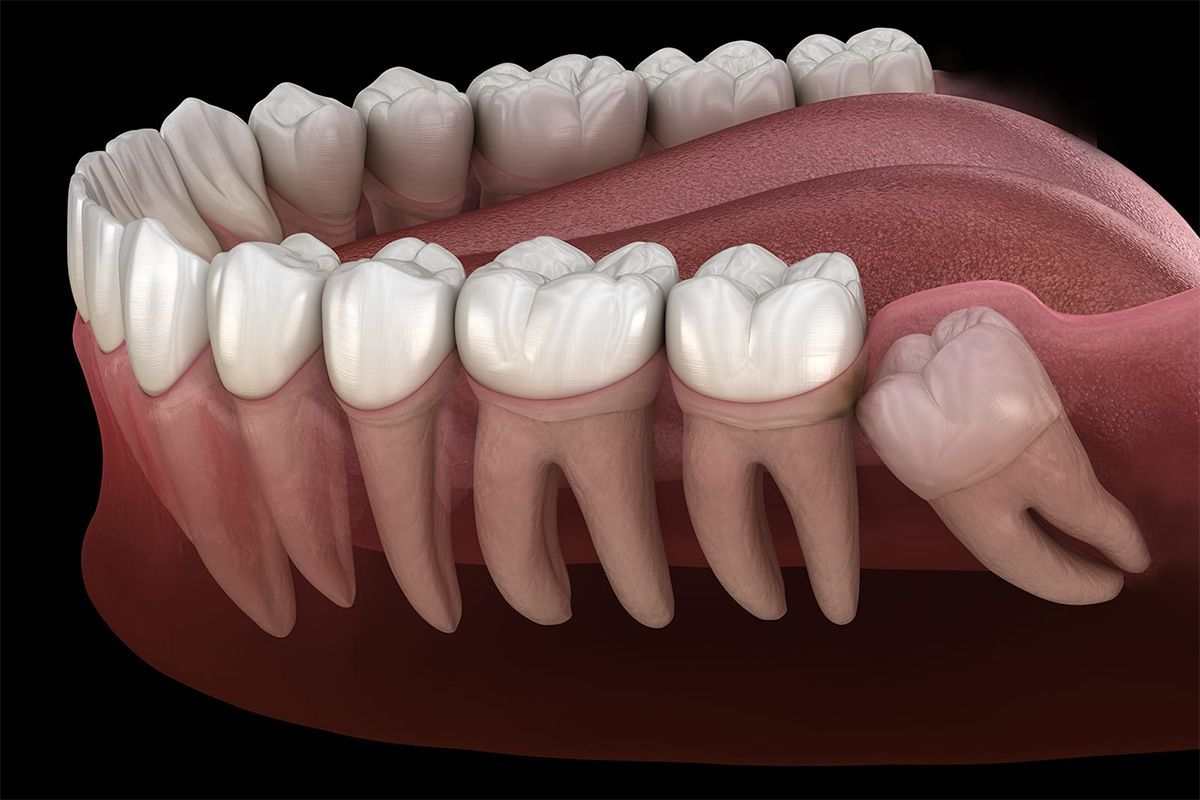

20 Yaş Diş Çekimi

20 yaş dişi; genelde 16-25 yaş aralığında çenenin iki tarafının sonunda olmak üzere toplamda 4 adet çıkan üçüncü büyük azı...

Devamını Oku

Gömülü Diş...

Gömülü dişler, ağız cerrahisinde en sık görülen olgulardır. Ağızda sıklıkla alt-üst 20 yaş dişleri, üst çene köpek dişleri ve...